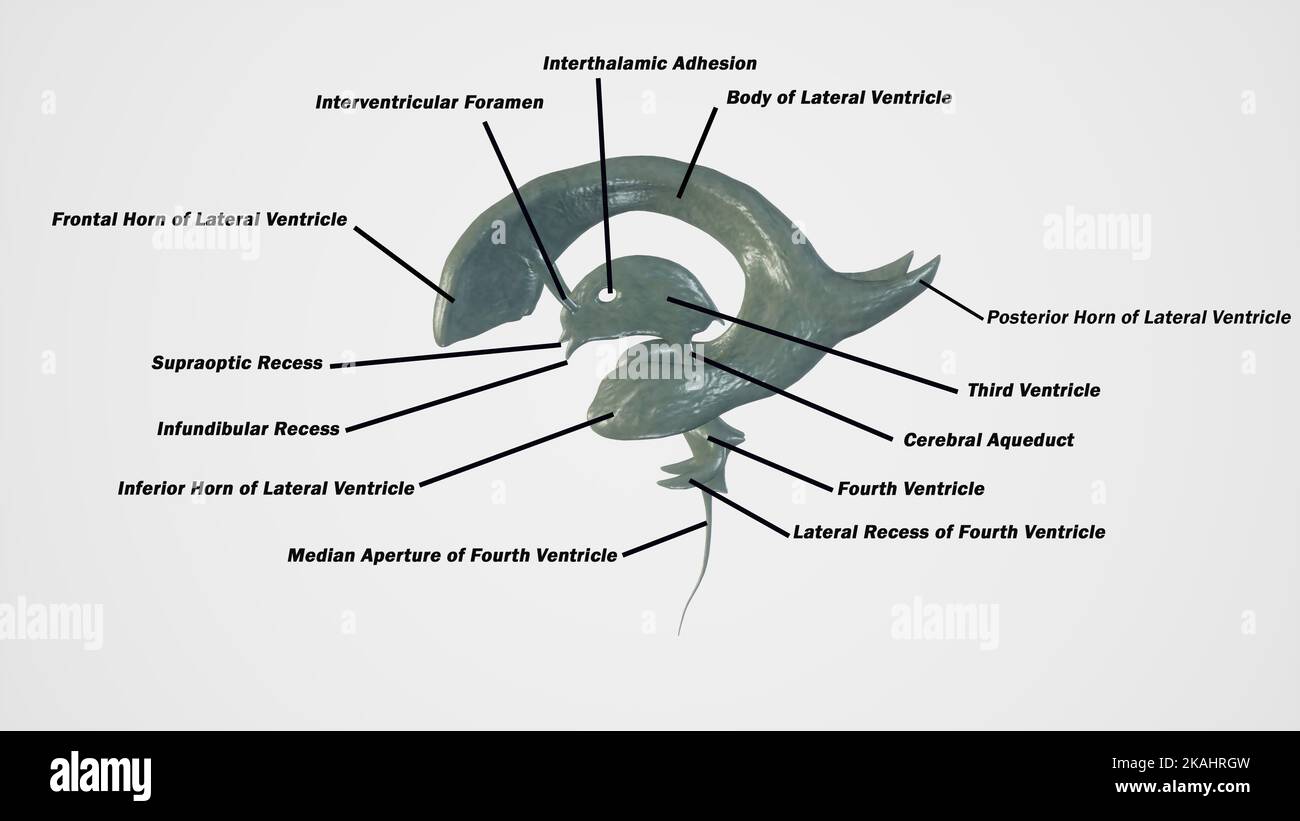

RM2AWF8JC–Die Anatomie des Nervensystems, vom Standpunkt der Entwicklung und Funktion. -Ant. HornCentra, Teil Latcral vnnInf. Horn Q virale Pari Ant. Horn. Ventrikel Ventrikel Ventrikel Ventrikel Ventrikel Ventrikel Ventrikel Ventrikel Ventrikel Ventrikel Ventrikel Ventrikel Ventrikel Ventrikel Ventrikel Ventrikel Ventrikel Ventrikel Ventrikel Ventrikel ^^ 176.-Zwei Ansichten der Hirnventrikel des Menschen: A, Dorsale Ansicht; B, laterale Ansicht. Das Vorderhorn oder Cornu anterius ist der Teil, der rostral zum interventrikulären Foramen liegt. Seine Dach- und Rostrallgrenze wird von Thecorpus callosum gebildet. Sein mediales

RM2AWFNN9–Menschliche Anatomie, einschließlich Struktur und Entwicklung und praktische Überlegungen d in einem sagittalen mesialen Abschnitt (Abb. 910) wird jede dieser Teilungen als mit einem Teil des Systems der Kommunikation von Räumen verwandt angesehen, die als die dritten Ventrikel des Lateralands, der Aquädukt von Sylvius und der vierte Ventrikel die oben genannten Gehirnhemisphären ausdehnen. Durch den Hirnstamm und unter dem Kleinhirn bis zum zentralen Kanal des Rückenmarks. Da die lateralen Ventrikel zwei innumerieren, ist die Theirstellung im Zusammenhang mit den Gehirnhemisphären, in denen sie liegen, lateral zum m

RM2AN4TWY–Handbuch der allgemeinen, beschreibenden und pathologische Anatomie (Band 2). Ventrikel, ein. Ventrikel des Kleinhirns, b. Aquädukt von Sylvius, C. Dritten Ventrikel, d. Lateralen Ventrikel, 1. Vordere Horn, 2. Hintere Horn, 3. Absteigend Horn, II. Textur, III. Gewicht, IV. Konsistenz, Kap. Iii. Umhüllt des Gehirns. Abt. Ich. Pia - mater, I. des Rückenmarks, II. Von Hirn, ein. - Externe Pia mater, b. Interne pia-mater, ich. Choroid Plexus des vierten Ventrikel, ii. Choroid Plexus des Großhirns, Art.ii.Apert-syndrom Membran, Art. hi. Dura-mater, I. spinalen Dura-mater, II. Zerebrale Dura-mater

RM2CDFE0C–. Elemente der physiologischen Psychologie; eine Abhandlung über die Aktivitäten und die Natur des Geistes, aus der physischen und experimentellen Gesichtspunkten. ide,die corpora quadrigemina. Die Kavität des Neuralrohres bleibt hier klein und bildet das Aquädukt, das den Viertmit dem dritten Ventrikel verbindet. Im Zwischenhirn dehnt sich das Aquädukt in den dritten Ventrikel aus; und hier wird wieder die dorsale Wand des Tubus zu einer breiten, dünnen Membran, die in den Ventrikel gefaltet und Blutgefäße mit sich trägt. Während die zerebralen Hemisphären ihr enormes Wachstum durchlaufen, dehnt sich die Kavität mit ihnen aus, andrema